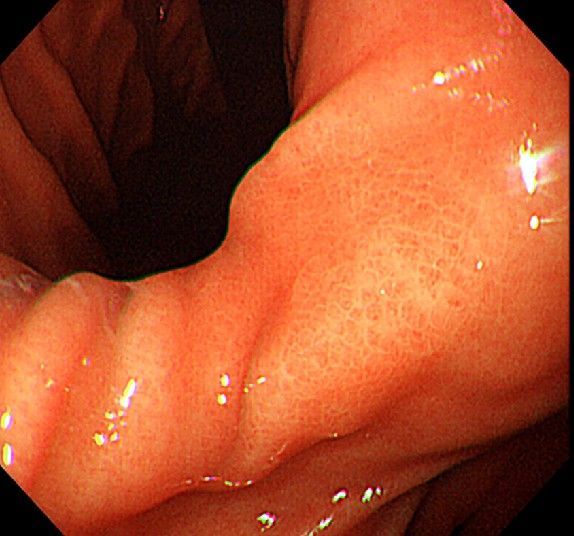

위 내시경을 찍었는데 위염 종류 사진을 알 수 있을까요? (사진 많습니다..)

한달 전 쯤에 소화불량과 속쓰림이 3개월 동안 약을 먹어도 낫지 않아 위 내시경을 찍었는데 위에 염증이 많이 있다는 이야기를 들었습니다...그런데 상태가 얼마나 안 좋은지 어떤 종류의 위염인지에 대해서는 물어봐도 안 알려주셔서 여기에라도 올려서 여쭈어봅니다... 제 상태가 얼마나 심각한 걸까요..

사진상으로 보아서는 정상에 가까운 점막상태이거나 약간의 표재성 위염이 있는 정도로 보입니다.

홍반성 위염이 있으며 경증의 역류성 식도염이 있습니다